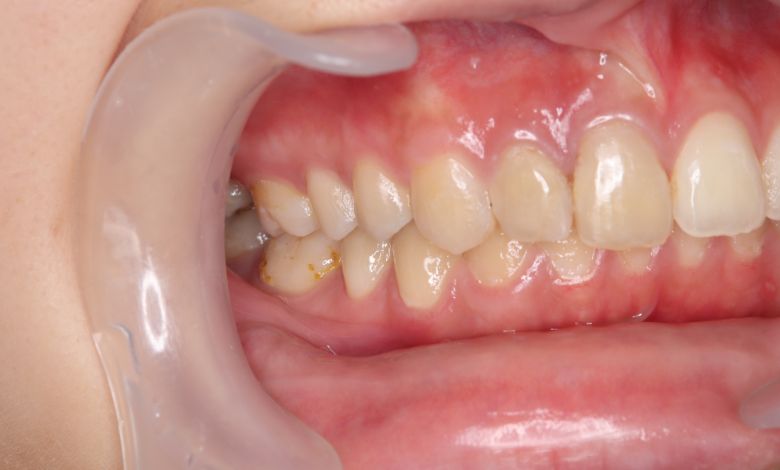

叢生が解消され、歯列全体にわたり滑らかで調和のとれた配列が得られています

上下の前歯の重なりが解消され、歯軸の傾きも整いました。咬合関係も安定しています

歯列弓はV字型から自然でゆったりとしたU字型へと広がり、唇側に転位していた犬歯も正しい歯列内に整列されています。

上下の前歯の重なりや段差は完全に解消され、咬合関係も安定してる。自然なスマイルラインが形成され、口元の印象も大きく改善された